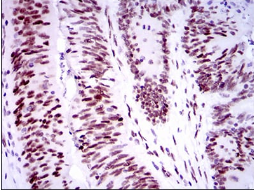

TP53BP1 Mouse Monoclonal antibody[6B3E1]

Species Reactivity:    Human

IHC    1/200 - 1/1000